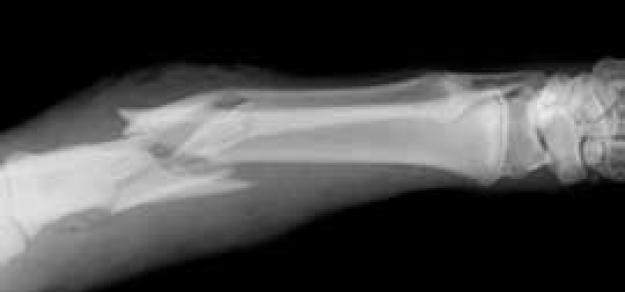

Evaluación de la asociación de determinantes genéticos y clínicos para el riesgo de fractura

BMJ, 29 de agosto de 2018 El metaanálisis identifica 15 determinantes genéticos de la fractura, que todos también influyen en la densidad mineral ósea. Entre los factores de riesgo clínicos para la fractura evaluados, solo la densidad mineral ósea muestra un efecto causal importante en la fractura. La predisposición genética a niveles más bajos de vitamina D y la ingesta estimada de calcio de fuentes lácteas no se asocian con el riesgo de fracturas.